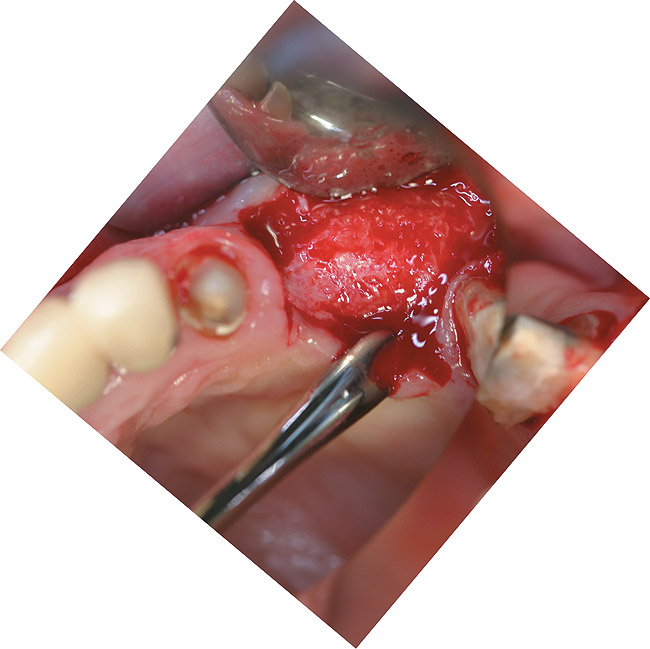

Figure 12  Occlusal view of the lost facial plate after flap reflection.

Figure 12